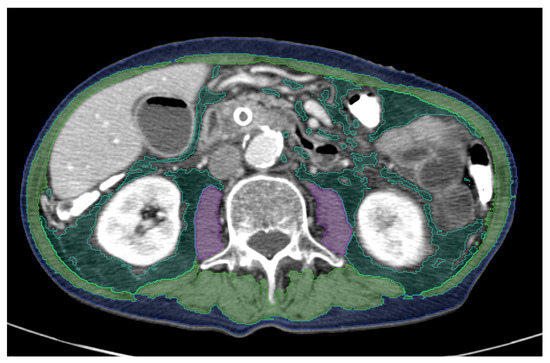

2.4. AI-Based Body Composition Analysis

- Beetz, N.L.; Maier, C.; Segger, L.; Shnayien, S.; Trippel, T.D.; Geisel, D.; Fehrenbach, U. First PACS-integrated, artificial intelligence-based software tool for rapid and fully automatic analysis of body composition from CT in clinical routine. JCSM Clin. Rep. 2021, 7, 3–11. [Google Scholar] [CrossRef]